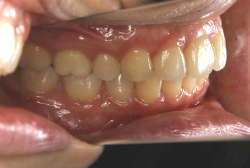

上顎前突

上顎前突(出っ歯)とは上顎が前に出ている状態です。この症状の特徴は、上下の歯並び全体の位置関係が相対的に上顎が優位になっていて、前歯が外に反っているだけでなく奥歯の位置関係も上が前にズレています。さらに凸凹の症状も合併していることがよくあり、上の前歯の見た目を気にして来院する方が多いのですが、実は今言った理由で噛み合わせにも異常があるため、このまま放置すると顎関節症という症状が出ることもあります。

「出っ歯を治したい」という主訴で来院したケースです。診断の結果、「2級1類の上顎前突+軽度叢生」と判明しました。2級というのは、基本的に出っ歯の噛み合わせになっていることを言います。その中でも上の前歯が著しく外に反っているケースを、「1類」といいます。初診時の横向きの写真を見ると、それがはっきり分かります。上の前歯に押されて唇も膨らんで、審美線をかなりオーバーしています(審美線とは、鼻の先端と顎の先端を結ぶ線のことで、この線よりも唇は内側にある方が良いとされています)。

このような症状の場合は、前歯を内側に入れるためにかなり大量の隙間を必要とします。通常は上下左右の小臼歯を抜歯させていただくのが正解です。治療後は歯の角度が正しくなっただけでなく、唇の審美性が大幅に改善しました。もちろん噛み合わせ的にも正しい状態が確立しています。